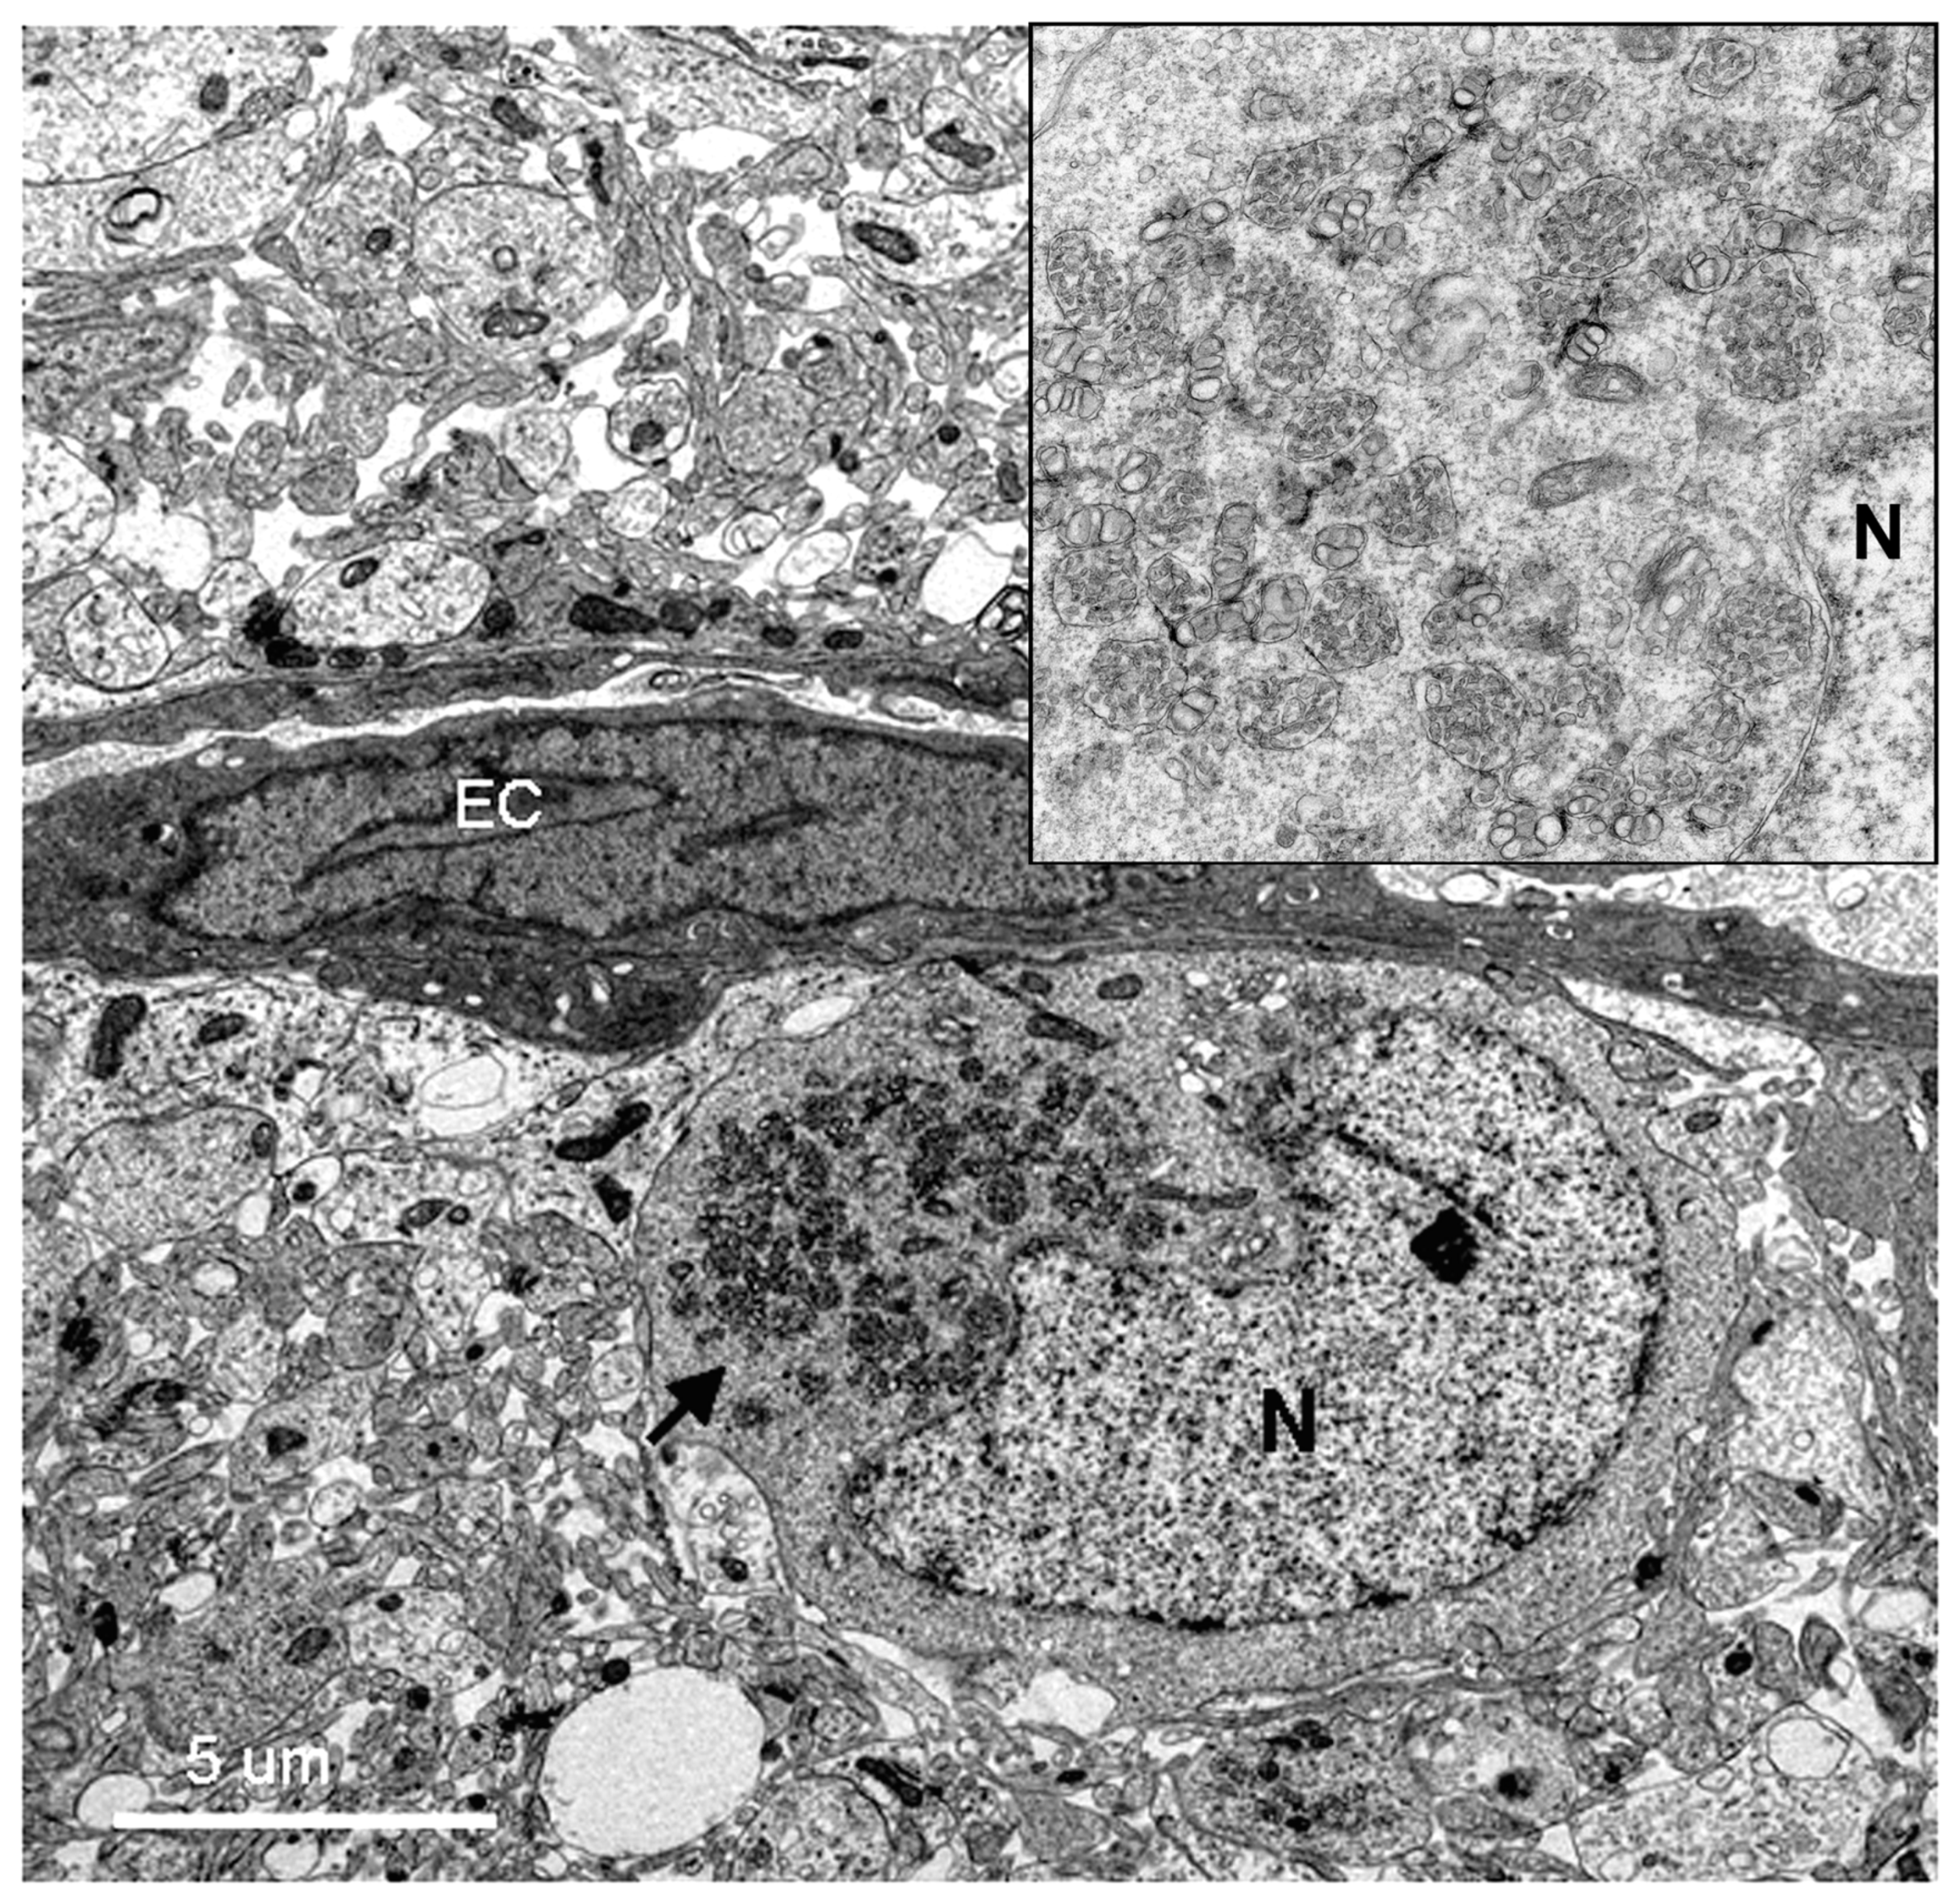

Figure 6. Low resolution electron micrograph of a DV-infected neuron near an endothelial cell lining capillary (EC). The perinuclear region of the cytoplasm of the neuron is filled with packets of virus-induced membranes (arrow pointing to high resolution inset at upper right corner). The packets are circumscribed by membranes. The nucleus and nucleolus (N) appear normal with intact nuclear membranes.

3.2. Infection of the Suckling Mouse Brains

All DV-infected SMB gave positive immunohistochemistry results with serotype-specific monoclonal antibodies [8], whereas controls were all negative for viral antigens (Figure 5). Neurons and microglia consistently showed signs of infection but no differences in pathological features were found amongst different serotypes. Neuronal, not endothelial cells showed packets of virus-induced membranes in perinuclear region of the cytoplasm (Figure 6). Alteration of the ER was the most conspicuous cytoplasmic change. The ER became more prominent, numerous and distended into cisternae containing closely packed vesicles of different shapes and contents. Some enlarged envelope-containing virions could also be identified (Figure 7A,B). Virus-induced ER membrane structures aggregated around the perinuclear region. The structures consisting of double membrane vesicles, densely packed convoluted membrane aggregates (CM), closely associated with dilated ER containing multiple vesicles or vesicular packets (VP), and round vesicles containing clusters of virions were found in the DV-infected mouse brain (Figure 8; CM and VP were described in Reference [3]). These features have recently been defined by a series of in vitro DV-infected cell culture studies that culminated in a list of hallmark features unique for DV and its closely associated flaviviruses [3]. Our results demonstrated that these features also occur in an in vivo infection of a mouse brain.